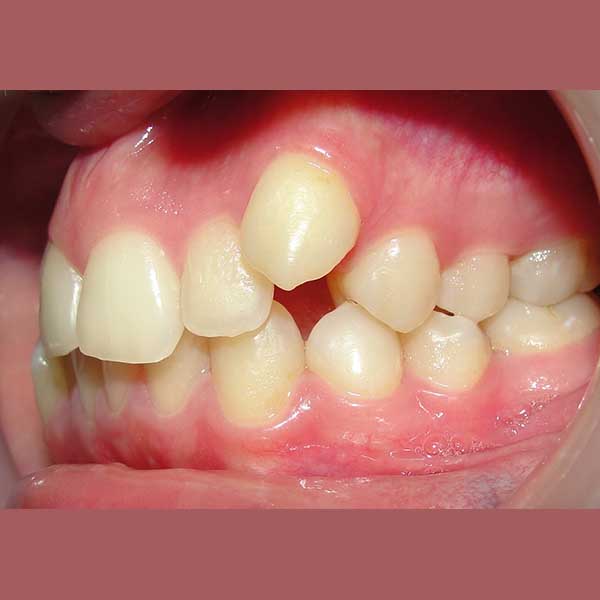

راجعتني هذه الشابة وهي تعاني من ازدحام شديد في أسنانها، كان أبرز مظاهره بزوغ أحد أنيابها بشكل مرتفع وبعيد جداً عن مكانه الطبيعي في القوس السني. كان طلبها واضحاً: الحصول على ابتسامة مرتبة ولكن مع تجنب قلع أي أسنان.